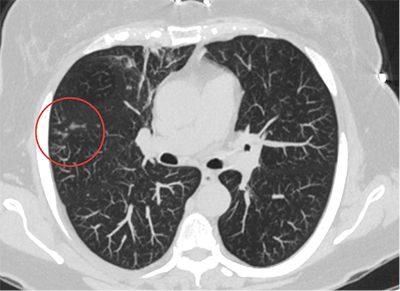

- Компьютерная томография высокого разрешения (КТВР) лёгких: Наиболее чувствительный метод для диагностики и оценки тяжести бронхоэктазов, их локализации и распространённости. Выявляет признаки хронического воспаления и слизистой пробки.

- Контроль состояния лёгких. Регулярное проведение компьютерной томографии высокого разрешения (КТВР) лёгких позволяет оценивать динамику бронхоэктазов, их распространённость и выявлять новые поражения. Функциональные лёгочные тесты (спирометрия) помогают контролировать функцию внешнего дыхания и эффективность терапии.